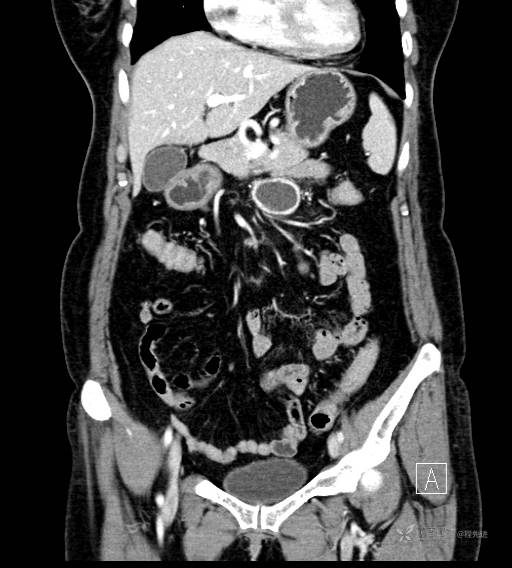

CT增强动脉期